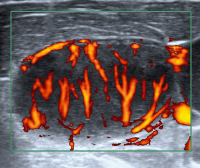

Lymphknoten-Ultraschall

Abbildung 1: Normalbefund, intranodale Gefäßarchitektur. Normalerweise sind die Lymphknotengefäße baumartig vom Hilus ausgehend. Die Verästelung ist regelmäßig. Die Gefäße sind am Außenrand des Cortex so klein, daß sie mit Farb- und Powerdoppler (derzeit noch) nicht erkennbar sind. In diesem Fall ist die Gefäßzeichnung nur minimal verstärkt im Rahmen einer infektiösen Mononukleose.